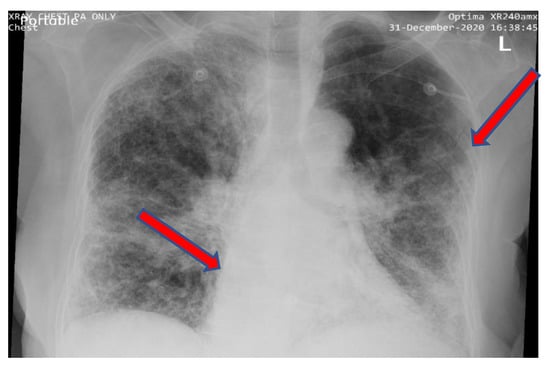

Since the emergence of COVID-19, due to the high number of deaths, many organizations in different countries have sought to develop rapid and accurate diagnostic methods. Given that COVID-19 causes distinct spots on the lungs—as shown by the sample in Figure 3—a radiological examination of the chest is an important tool that can be used in the diagnostic process [19]. CT scans play an essential role in diagnosing pneumonia, especially given their efficiency and accuracy in detecting the features of pneumonia. Accordingly, many prior studies (in Section 4.3) have used the CT scan modality for the examination and diagnosis of COVID-19 despite the fact that CXR is more appropriate for the process, for the following reasons: firstly, it is difficult to control the spread of infectious diseases in CT suites and to decontaminate CT scanning machines; secondly, CT scans are costly, and are not available in all hospitals; thirdly, CT scanners are not portable [21]. In comparison, CXR is portable, cheap, simple to perform, and available in most hospitals. Therefore, CXR is the most commonly applied method for the radiological examination of the lungs [22]. The American College of Radiology (ACR) recommends that portable chest radiography tools should be used to limit the risk of disease transmission when scanning COVID-19 patients [23].

Figure 3.

Pulmonary radiography of a person infected with COVID-19.